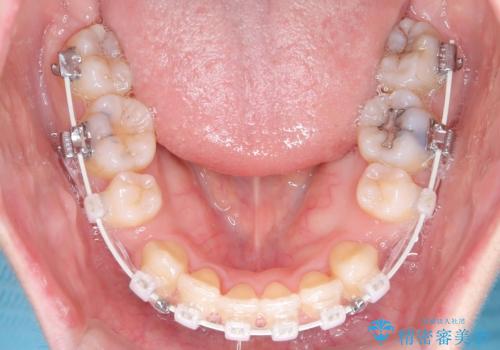

- 矯正装置

- ワイヤー(審美装置)

- 治療計画

- 「歯のデコボコと前歯が出ているせいで口が閉じにくい」を主訴に来院された患者様です。

上下左右の4番(第一小臼歯)を抜歯をし審美ワイヤー装置で治療を行いました。

抜歯矯正により歯列のデコボコ(叢生)が改善し、前歯の突出も解消されたことで口元が下がり、すっきりとした印象となりました。